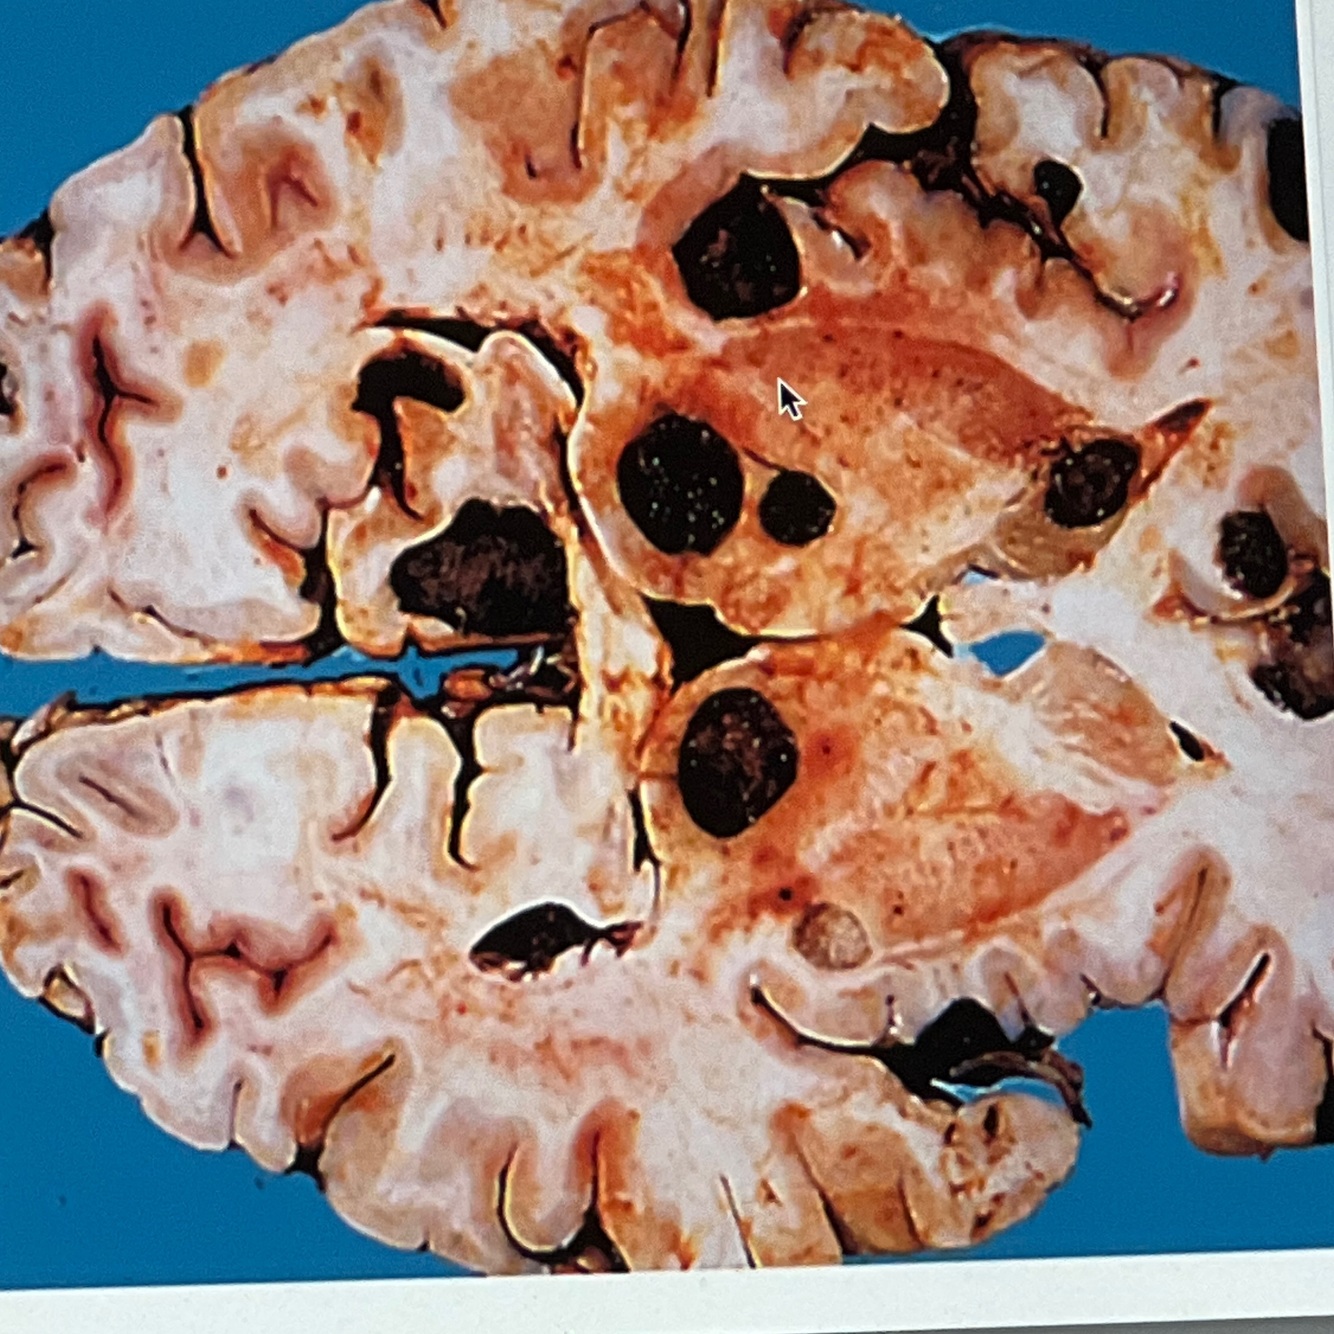

Diagnosis: metastatic deposits

Location: cerebrum

Multiple nodules of different sizes

Brown and friable with areas of hemorrhage and necrosis